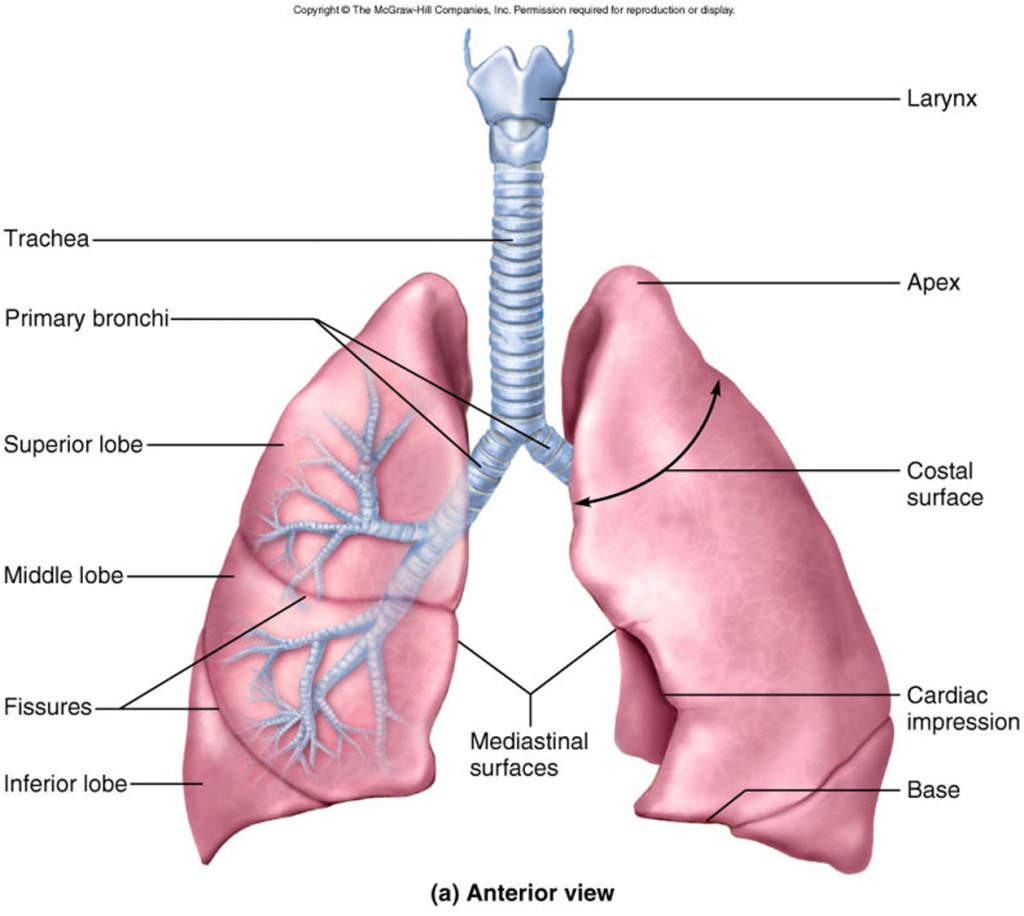

The Lungs | Anatomy And Physiology

courses.lumenlearning.com

courses.lumenlearning.com

lungs anatomy figure physiology gross labeled major